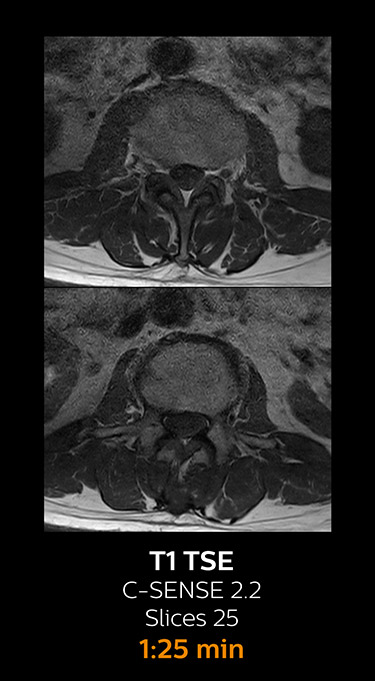

Fast MRI of cervical spine

With Compressed SENSE, the scan time for the routine cervical spine examination at KNC was reduced from 13:11 to 9:52 minutes, which corresponds to 25% reduction.

MRI examination of cervical spine with Compressed SENSE

MRI examination of the cervical spine with Compressed SENSE

Ingenia 3.0T CX

Scan time 9:52 min. (was 13:11 min. without Compressed SENSE)